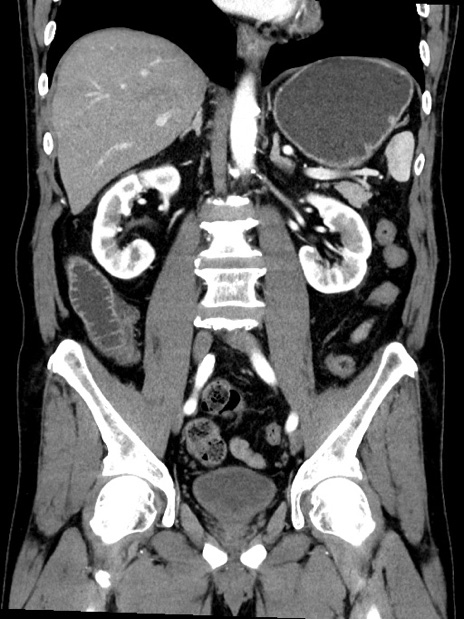

症例35(冠状断像)

【症例】70歳代 男性

【主訴】腹部膨満、嘔吐

【現病歴】昨日より腹部膨満感出現。本日増悪し、仙痛出現。嘔吐あり、受診。

【既往歴】糖尿病、胆摘後

【身体所見】BP 149/80mmHg、HR 74/min、BT 35.9℃、腹部:膨満、軟、圧痛なし。腸雑音減弱あり。上腹部正中切開瘢痕あり。

【データ】WBC 13500、CRP 1.72